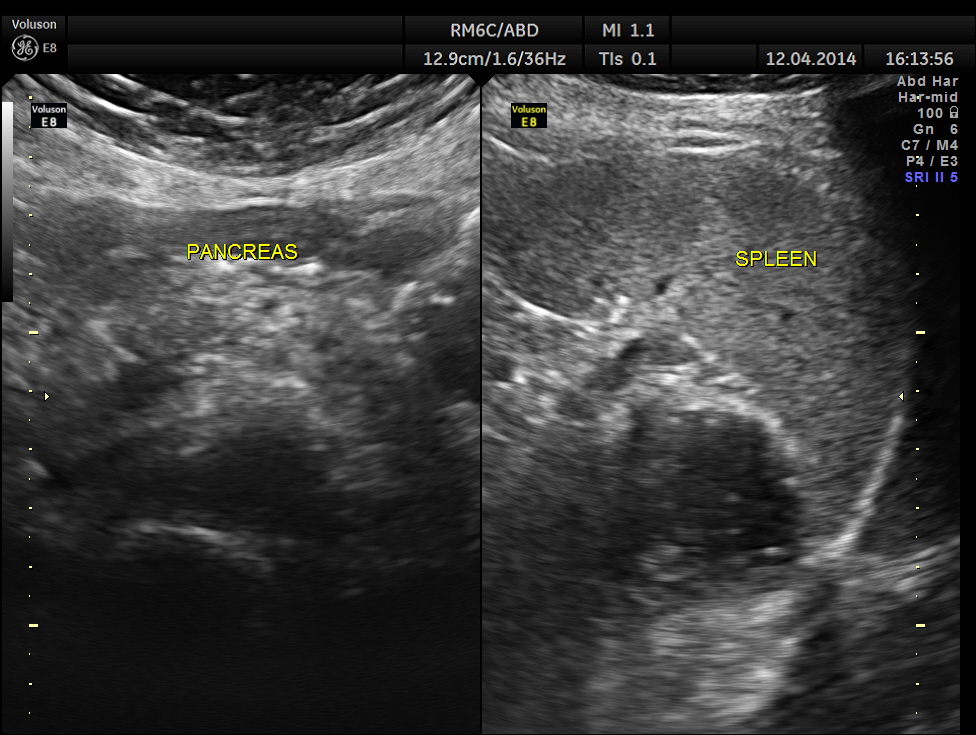

The following pictures show a normal liver, gall bladder, pancreas and spleen .